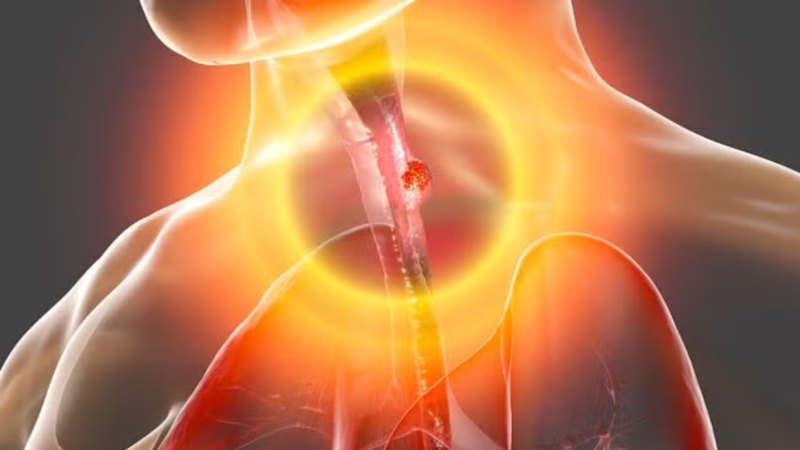

Esophageal adenocarcinoma is the seventh most frequent form of cancer and carries some of the highest mortality rates, due to modern Western diets and lifestyle factors. As such, the market potential for PromarkerEso as a diagnostic tool is enormous.

With throat cancer still claiming far too many lives through late detection, PromarkerEso’s breakthrough could mark a turning point in global cancer care.

By offering a quick, accurate and non-invasive blood test that rivals or even improves traditional diagnostic methods, Proteomics International is opening the door to earlier treatment and better survival rates while gearing up for an assault on the multibillion-dollar diagnostics market.